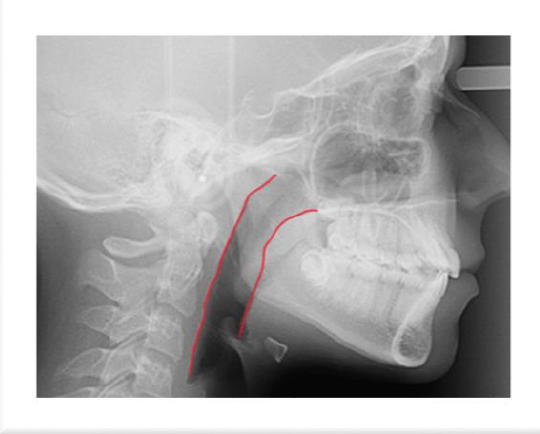

Zdjęcie cefalometryczne z widocznym powiększonym migdałkiem gardłowym zwężającym drogi oddechowe. Widać też cień języka nieprzylegającego do podniebienia oraz mocno napięte mięśnie bródki związane z dużą trudnością w zamknięciu ust. Kąt podstaw kostnych szczęki i żuchwy znacznie powiększony z żuchwą rotującą do dołu i tyłu. Wydłużony dolny odcinek twarzy.